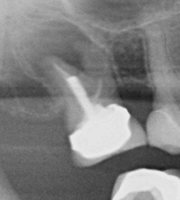

On your initial appointment the dentist will locate the offending tooth and take an x-ray in order to show the roots of the tooth, to see how far the decay has travelled and if there is an abscess present. A course of antibiotics may be given to clear the abscess before the treatment is started as the abscess will reoccur if the treatment is NOT carried out.